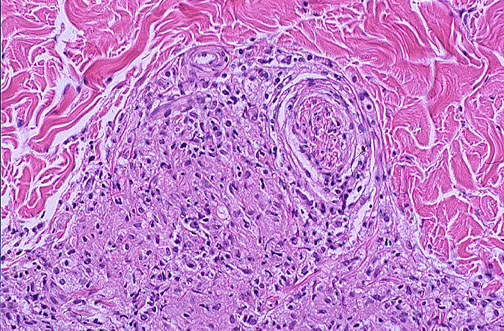

| This granuloma is seen around a peripheral nerve in the dermis. The lepra bacilli grow best just below body temperature, preferring the cooler skin and peripheral nerves. Hypopigmented patches or macular lesions with decreased sensation are seen on face, extremities, and trunk. Nodular disfiguring lesions can appear with the lepromatous form. |